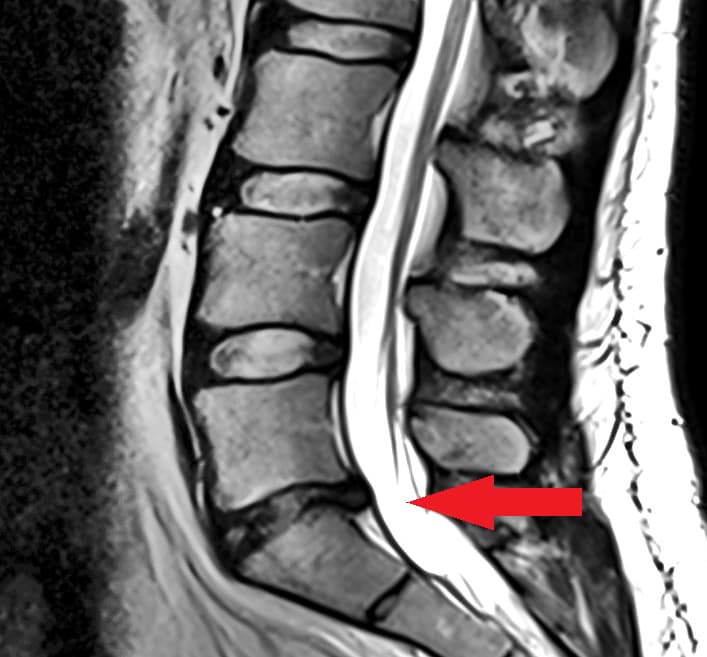

I’m pretty sure I’ve shared in a trip planning thread or somewhere on here that I haven’t been running since July 2023 due to a herniated L5-S1 disc. See image below. Well, after seeing 3 spinal doctors, doing PT, and LOTS of procrastinating I’m finally pulling the trigger on disc replacement surgery. What has finally pushed me over the edge is my inability to sleep. I’m waking up like 10 times a night, no joke (see 2nd image below). I need sleep. But I also need to run.